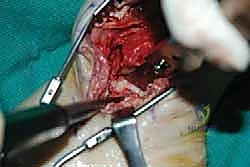

5. إدخال وتثبيت الصفيحة النصلية (Blade Plate)

هنا تكمن المهارة الجراحية الفائقة. يتم تشكيل مجرى دقيق داخل عظمة الكعب باستخدام إزميل خاص، ثم يتم طرق "نصل" الصفيحة المعدنية بحذر شديد داخل عظمة الكعب لضمان أقصى درجات الثبات.

6. التثبيت النهائي بالبراغي (Screw Fixation)

بعد التأكد من الموضع المثالي للصفيحة والنصل، يتم تثبيت الجزء العلوي من الصفيحة على عظمة قصبة الساق باستخدام براغي قشرية (Cortical Screws) قوية. يتم وضع العظام تحت ضغط ميكانيكي (Compression) لتحفيز الخلايا العظمية على الالتحام السريع.